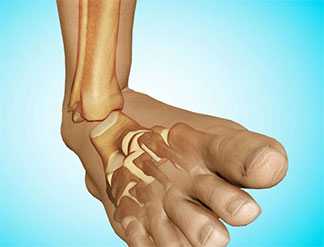

Голеностопный сустав - сложное анатомическое образование, состоящее из трех костей. В него входят больше- и малоберцовая, а также таранная кости. Благодаря этому сочленению происходит передача нагрузки от всего тела к стопе, обеспечивается амортизация при ходьбе, беге, прыжках и ряде других интенсивных движений. Также именно благодаря ему человек может похвастаться высокой подвижностью стопы и, как следствие, хорошей маневренностью.

В норме голеностопный сустав - соединение, стабильность которого обеспечивается связками. Связки располагаются не только на внешних, но и на внутренних поверхностях сустава. Благодаря ним обеспечивается не только стабильность сустава, но и соединение с костями стопы.

Строение голеностопа: кости, сышцы и связки.